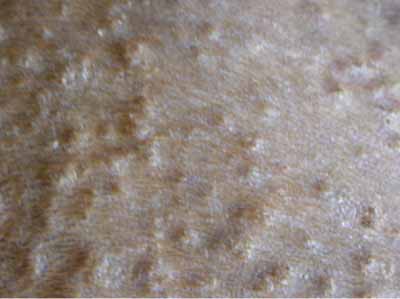

Photo 2 : Atteinte de l’ensemble du corps

©Photo Dr Jacques Lamothe.

Photo 3 : Lésions papulo-pustuleuses en face interne des postérieurs

©Photo Dr Jacques Lamothe.

Photo 4 : Lésions papulo-croûteuses et discret squamosis pityriasiforme amiantacé

©Photo Dr Jacques Lamothe.

Photo 5 : Lésions papulo-croûteuses excoriées et collerettes épidermiques

©Photo Dr Jacques Lamothe.

Photo 6 : Lésion pustuleuse

©Photo Dr Jacques Lamothe.